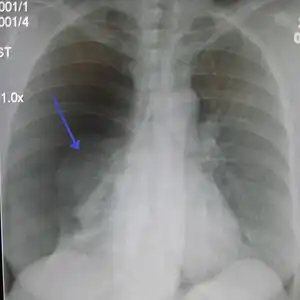

Pneumotorax

Diagnosticul se bazează pe apariția brutală a dispneei, durerea toracică violentă și atroce, fenomenele grave de asfixie, abolirea vibrațiilor vocale, hipersonoritate și tăcere la auscultație. În cele mai multe cazuri, pentru diagnostic se folosește radiografia toracică. Medicul specialist poate recomanda, de asemenea, analize sangvine care măsoară nivelul oxigenului din sânge. Tomografia computerizata (CT) sau ecografia pot fi necesare la diagnosticul severității bolii și la alcătuirea schemei de tratament.